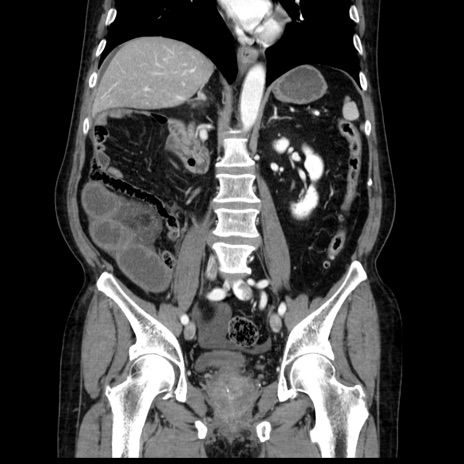

症例30(冠状断像)

【症例】80歳代男性

【主訴】臍周囲痛

【現病歴】約6時間前から臍下部痛が出現。次第に腹部膨隆・背部痛も生じてきたため来院。背部痛の場所は変化しない。

【身体所見】意識清明、BT 36.3℃、BP  131/87mmHg、P 87bpm、SpO2 100%(RA)、臍周囲自発痛・圧痛あり、反跳痛なし、自発痛部位に一致して板状硬あり、腹部膨隆、腸雑音減弱、CVA tenderness両側陰性。

【データ】WBC 19600、CRP 0.33